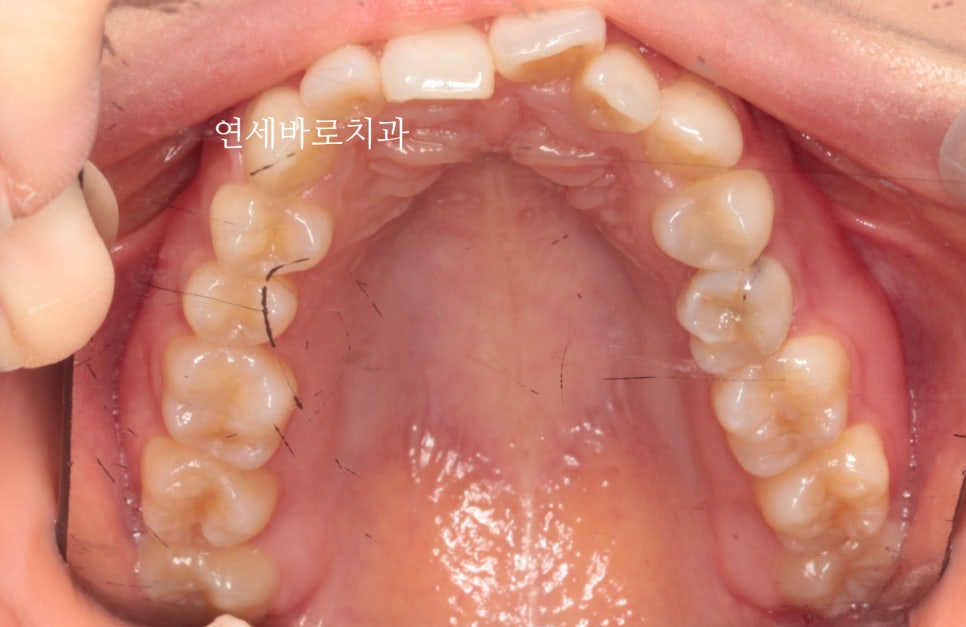

심한 덧니와 과개교합을 보이고 있는 환자분입니다.

그리고 한개 치아의 #선천적결손 이 관찰됩니다.

화살표 부위가 결손치아입니다. 유치가 남아있네요.